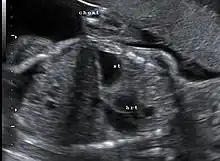

![]() | |

| Morgagni hernia seen on a chest radiograph. | |